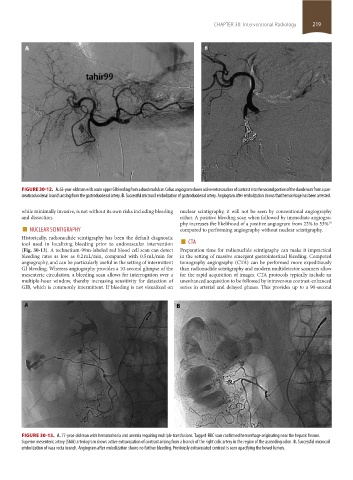

FIGURE 30-12. A. 63-year-old man with acute upper GI bleeding from a duodenal ulcer. Celiac angiogram shows active extravasation of contrast into the second portion of the duodenum from a pan-

creaticoduodenal branch arising from the gastroduodenal artery. B. Successful microcoil embolization of gastroduodenal artery. Angiogram after embolization shows that hemorrhage has been arrested.